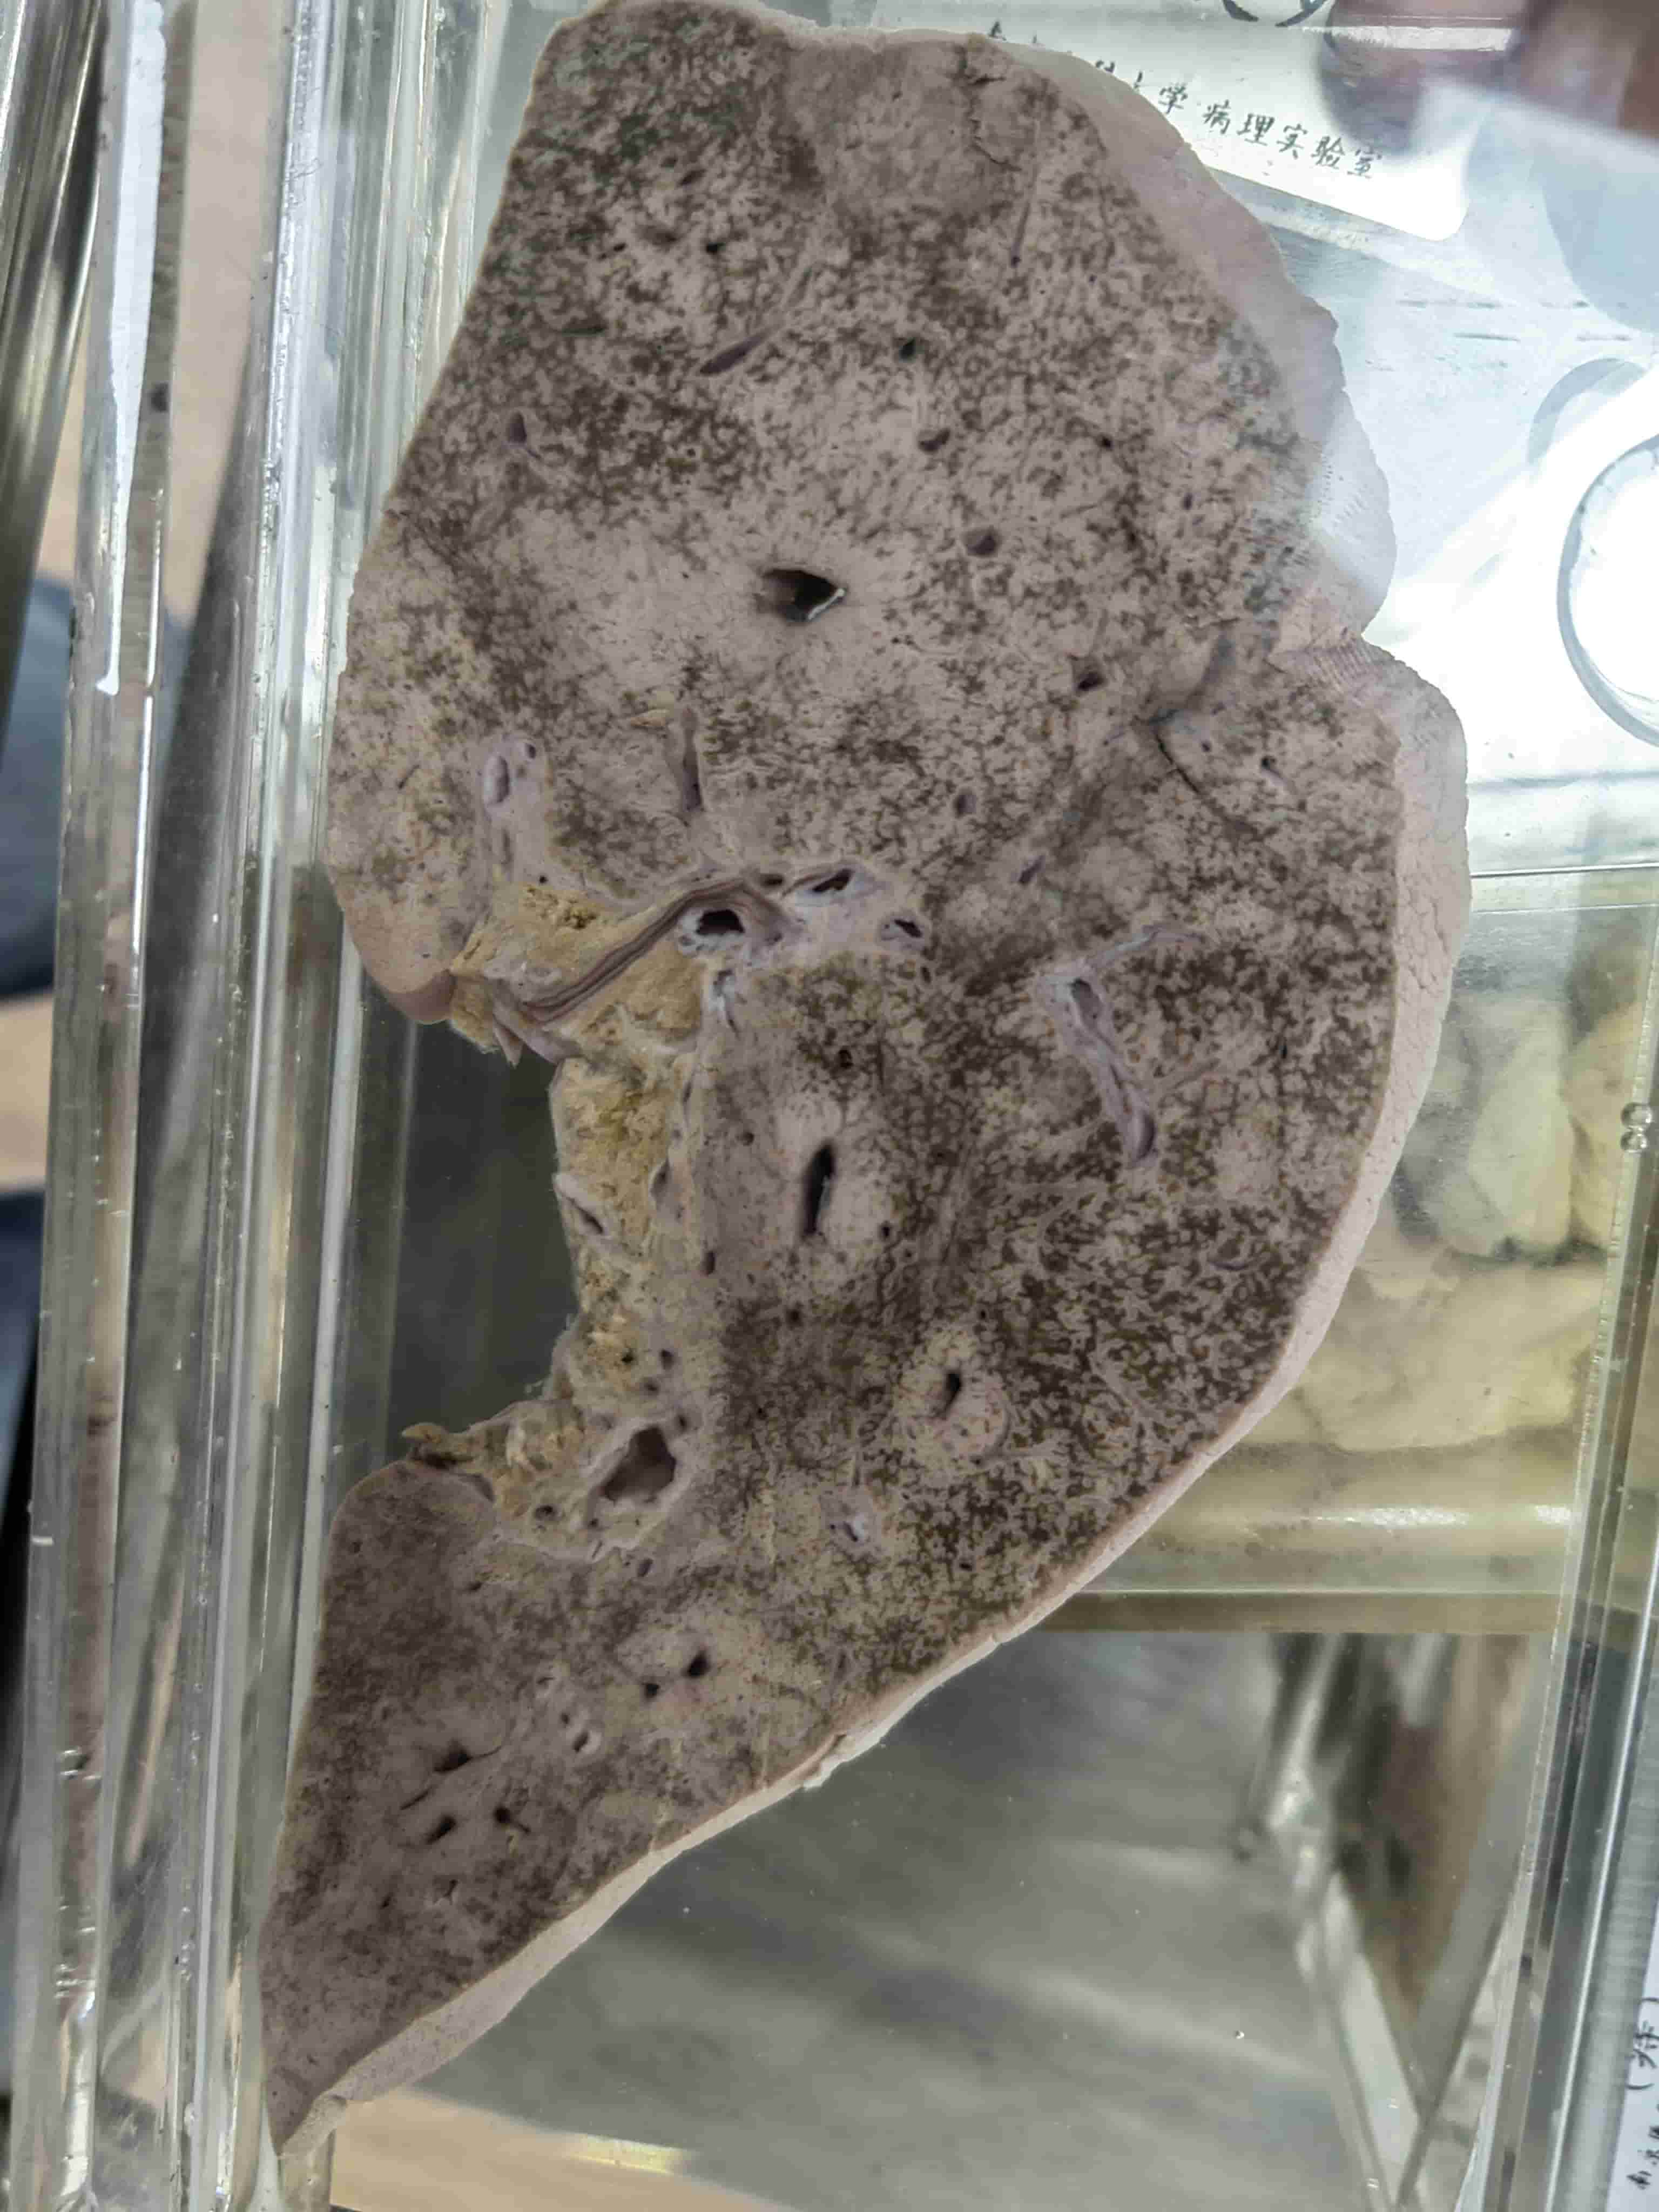

硅肺.0.0

硅肺.0.1

硅肺.0

硅肺.1

硅肺.2

硅肺